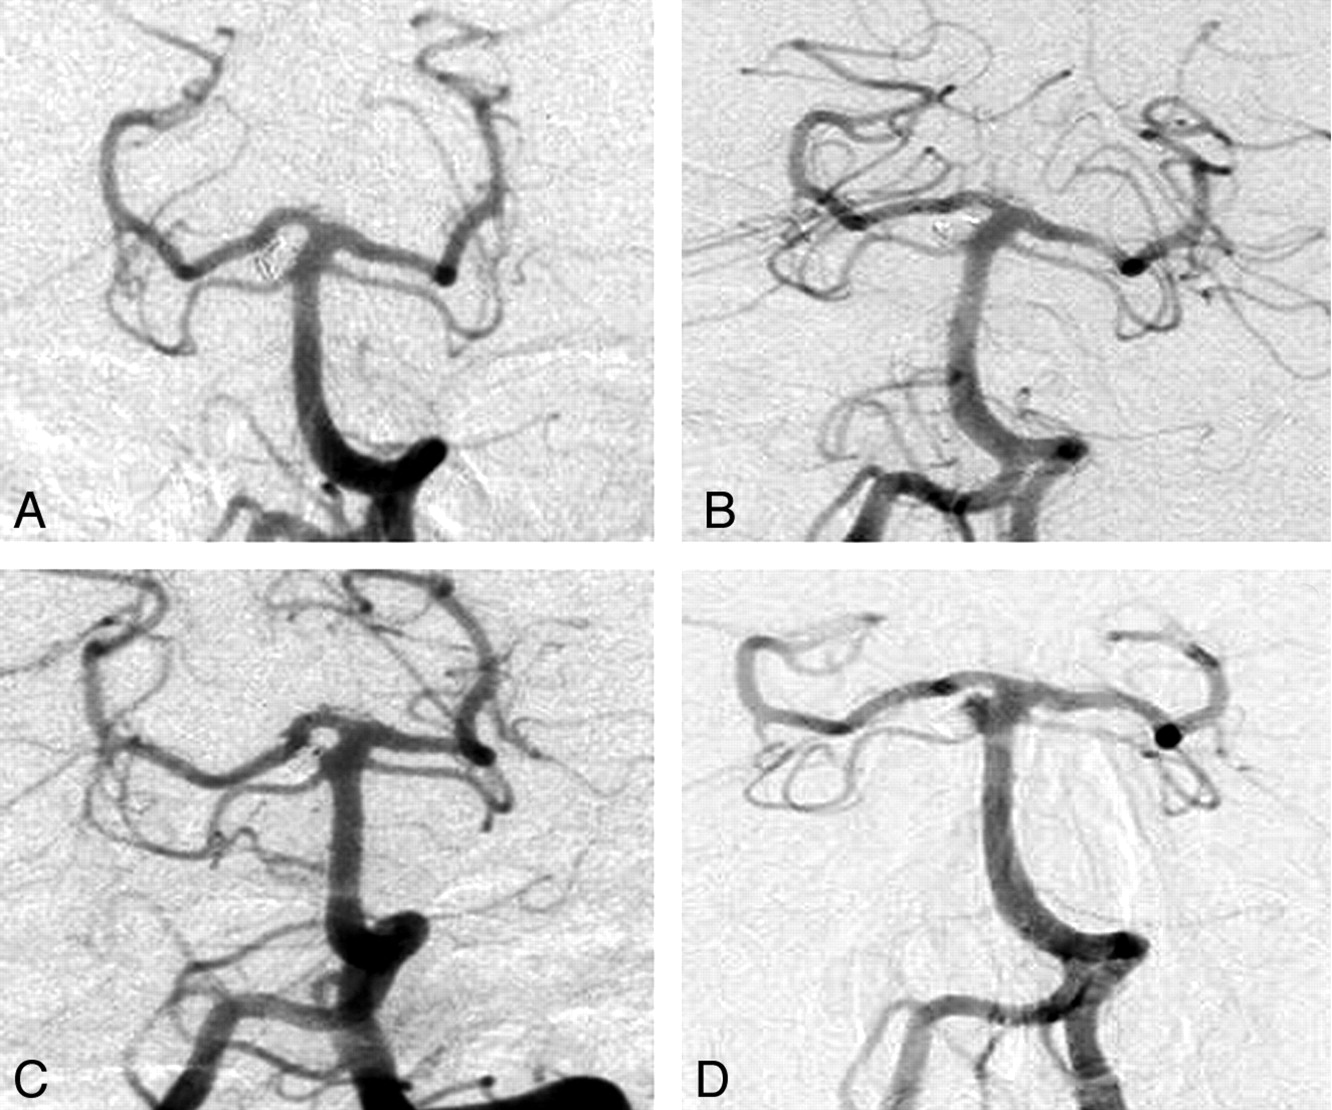

The last reason is factual: I have repeatedly witnessed patients with βstableβ complete or near-complete occlusions for many follow-up examinations, only to have them show up years later with recurrences (Fig 1).7 It is true that, grosso modo, 2 types of recurrences can perhaps be distinguished: 1) a more problematic, more frequent, premature type, detectable at 6 months; and 2) a delayed type became more than anecdotal only when follow-up studies were performed 3 years or more after satisfactory occlusions.7 I am aware that some teams, evoking a different mechanism, prefer to call these late recurrences βnew aneurysms at the same site,β but surely the problem cannot be evaded by giving it a different name.

Angiograms show satisfactory occlusion postcoiling (A) and stability at 2 years (B), only to have the aneurysms recur (minimally) 4 (C) and (significantly) 6 years later (D).